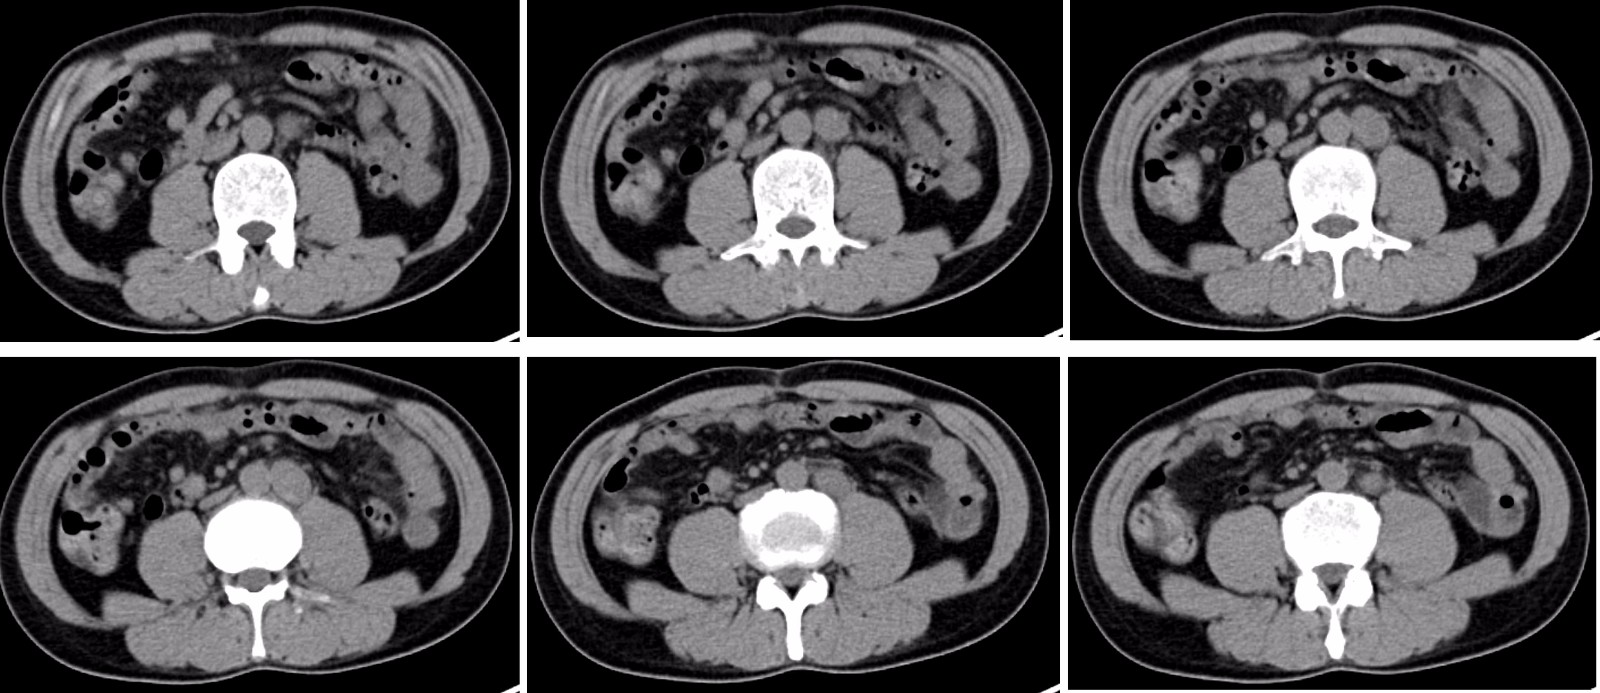

CT : 腹膜后淋巴结肿大,结合病史考虑为直肠癌转移。

2017.3.20 肿瘤抗原:CEA:6.89,AFP:1133.00。2017.3.20日起行XELOX方案化疗3次,末次化疗日期2017.5.3。期间2017.3.30腹部MR:腹膜后肿大淋巴结。2017.5.3 CEA: 14.59,AFP:2188。2017.5.12腹部MR:腹膜后肿大淋巴结,较前相仿。2017.5.17 PET/CT:直肠癌术后化疗后,腹膜后淋巴结转移,FDG高代谢;胆囊结石。